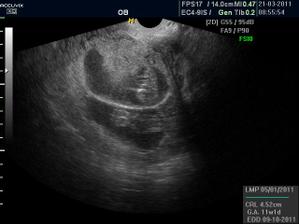

Pidižva č.2 a č.3... :o)

ahojky, no krásnýýýý, takže je to pravda, jak jsi mi psala, jupííí, jen houšť dvojčat 🙂)))))

@elis.1 elí je to krásný, ale to víš, trošku se bojím, aby bylo všechno v pořádku. Ale jsou nádherný a jak se mrskali...:o))) mi budeš muset dávat rady jak na dvojčata...:o)))